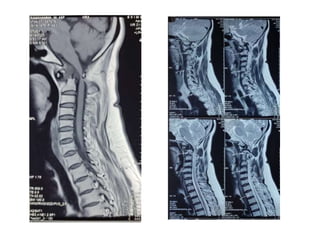

M Ramanamma is a 48-year-old female who presented with neck pain and paresthesias in her limbs for the past 5 months. On examination, she had decreased strength in her right upper and lower limbs and hypertonia in her lower limbs. Imaging showed atlantoaxial dislocation with compression of the cervical spinal cord at C1-C2, explaining her symptoms.